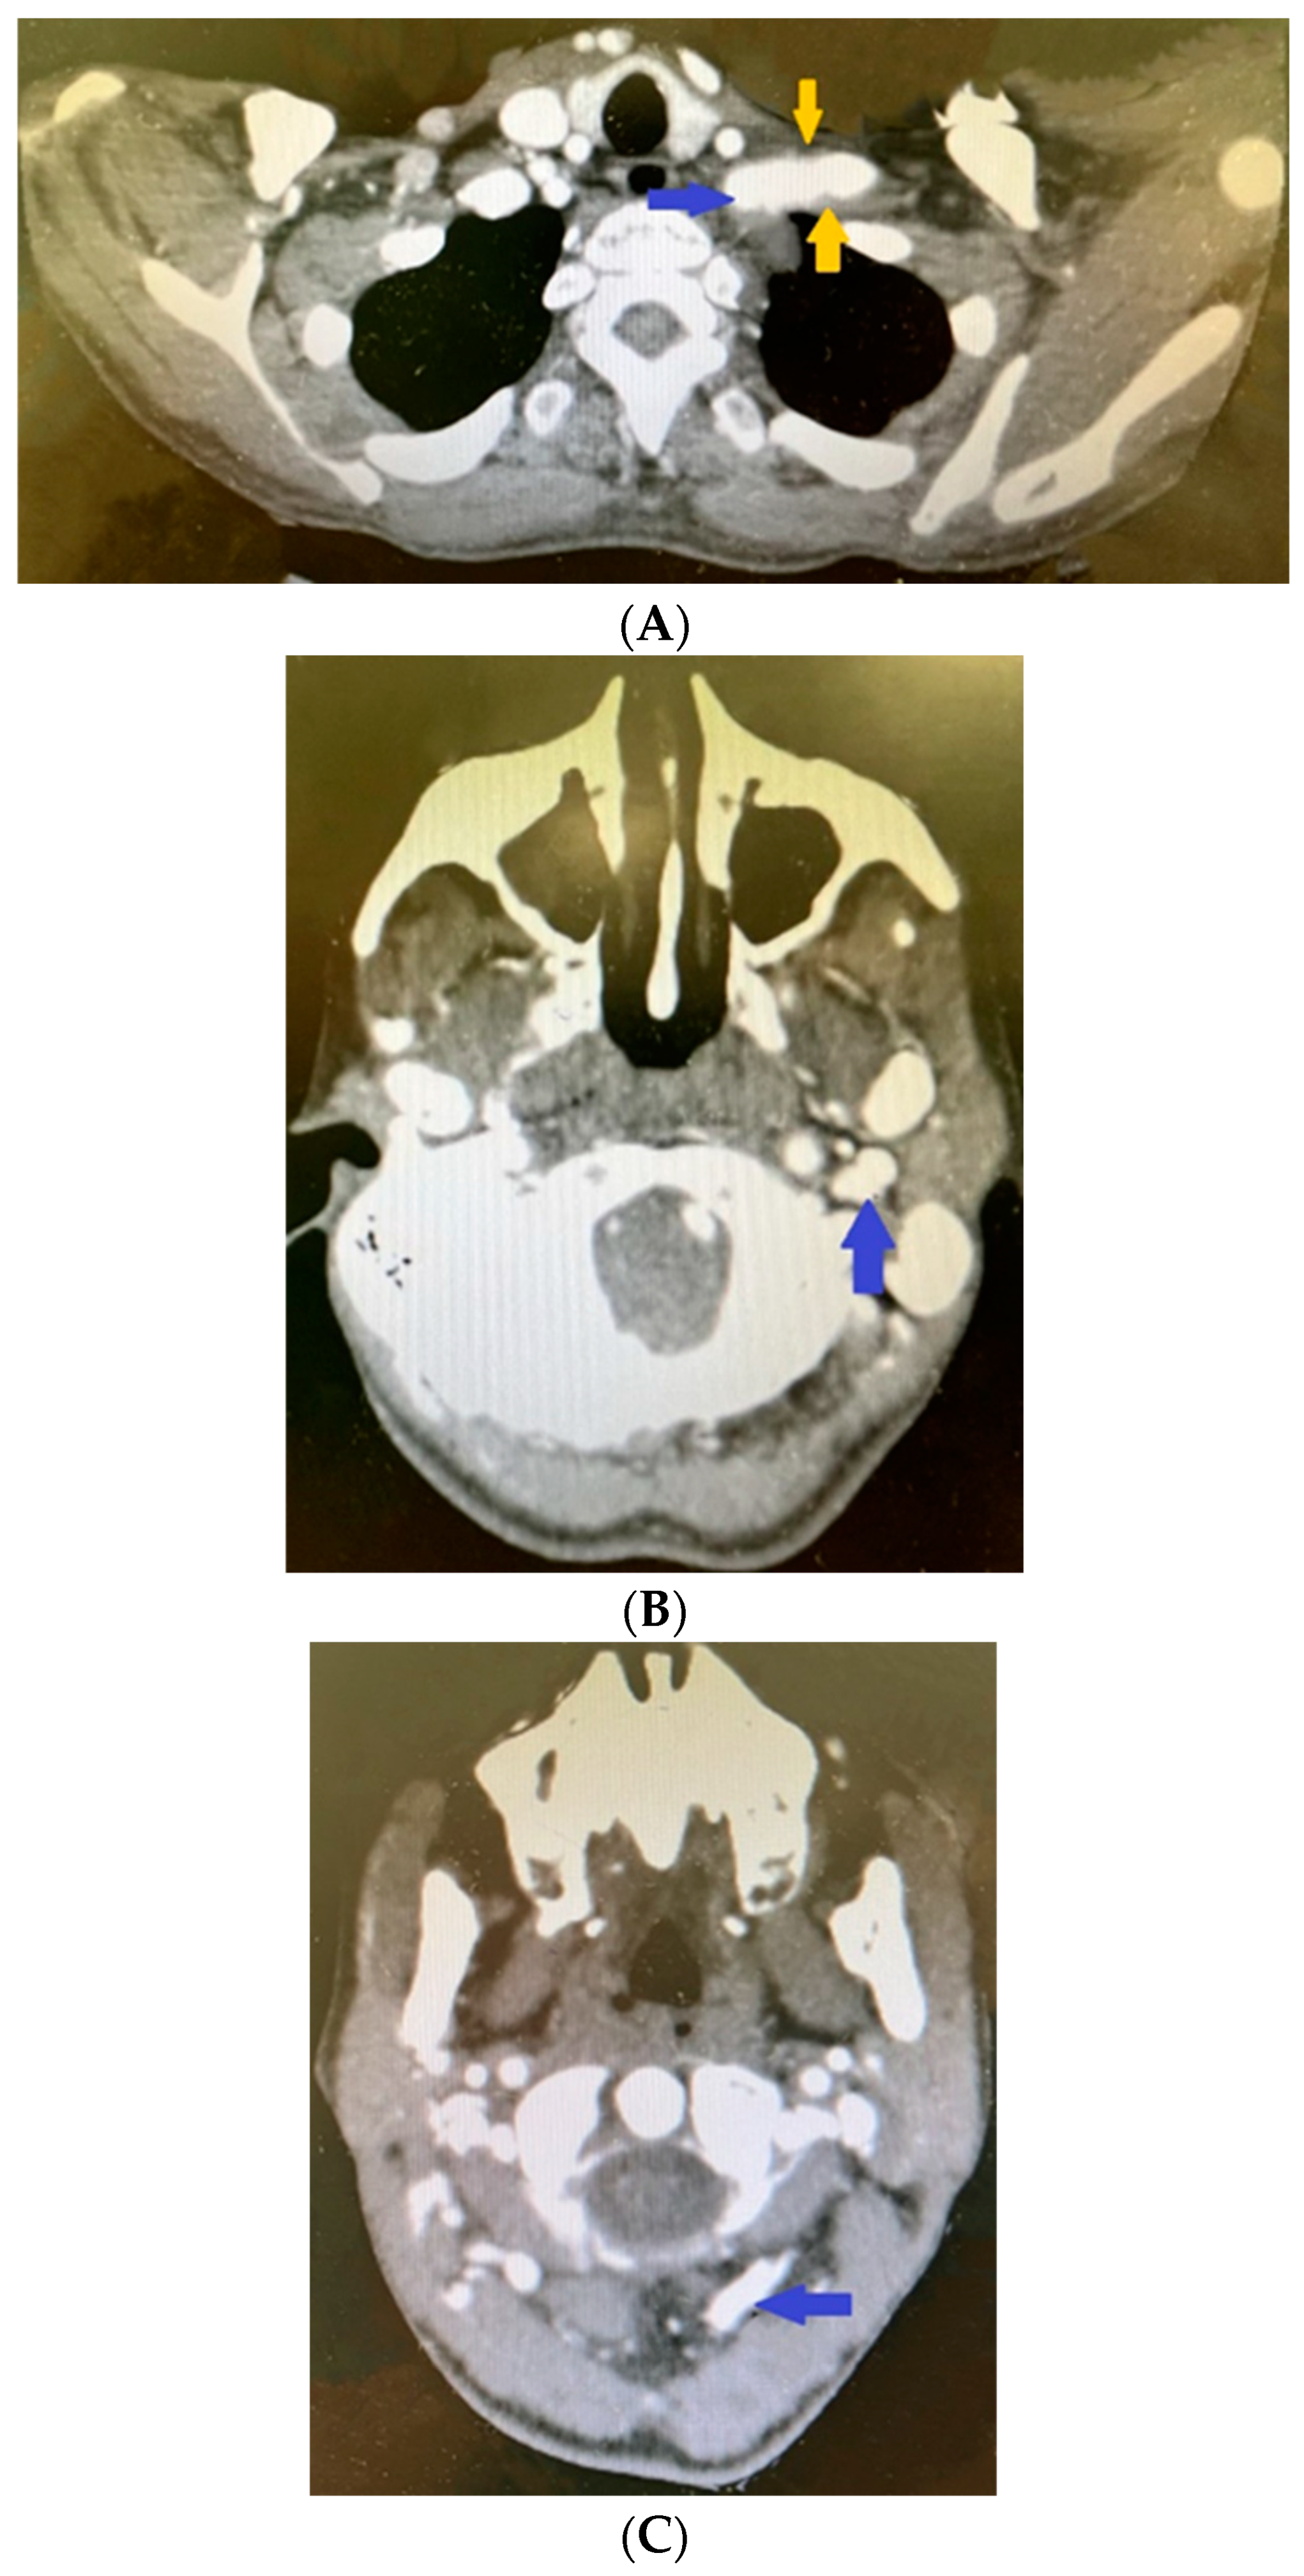

In addition, there was pathological involvement of the teeth in the patient. The pulp calcifications and obliteration of the pulp cavity revealed through radiography during an in vitro procedure (Figure 7A) made treatment of the asymptomatic granulomas impossible, and five teeth were extracted. The imaging study also revealed the spongy bone structure (Figure 7B) and some cystic masses (Figure 7C).

Figure 7.

Radiography revealing (A) pulp calcifications and obliteration of the pulp cavity; (B) spongy bone structure; (C) some cystic masses.